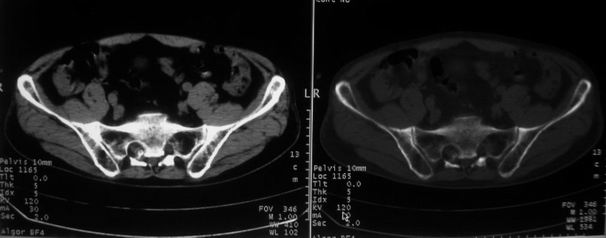

男,85岁,排尿困难。骶椎有问题吗?

前列腺明显增大,突入膀胱,各叶比例协调,密度均匀,精囊腺及精囊角正常;考虑良性增大。

骶骨没有看到明显异常。

1)考虑前列腺增生症并阻塞性膀胱炎。2)骶椎右侧类似囊状骨质密度减低区,边缘骨质硬化,其内为软组织密度影填塞,相邻之骶椎椎管受压变形;考虑为骶椎右侧囊肿或神经纤维瘤。

1)前列腺明显增大,突入膀胱,各叶比例协调,密度均匀,精囊腺及精囊角正常;考虑前列腺增生症并阻塞性膀胱炎。2)骶椎右侧类似囊状骨质密度减低区,边缘骨质硬化,其内为软组织密度影填塞,相邻之骶椎椎管受压变形;考虑为骶椎右侧囊肿或神经纤维瘤。

建议:行mri检查。